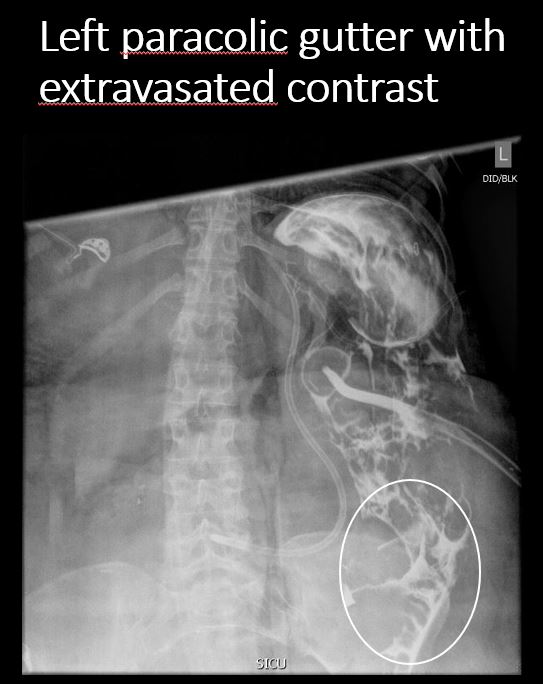

The paracolic gutters are abnormal. |

No | NA |